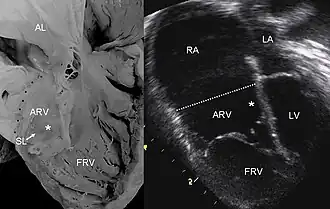

| Pathological specimen and ultrasound image of a heart with Ebstein anomaly. Abbreviations: RA: Right atrium; ARV: Atrialized right ventricle; FRV: Functional right ventricle; AL: Anterior leaflet; SL: Septal leaflet; LA: Left atrium; LV: Left ventricle; asterisk: grade II tethering of the tricuspid septal leaflet. | |